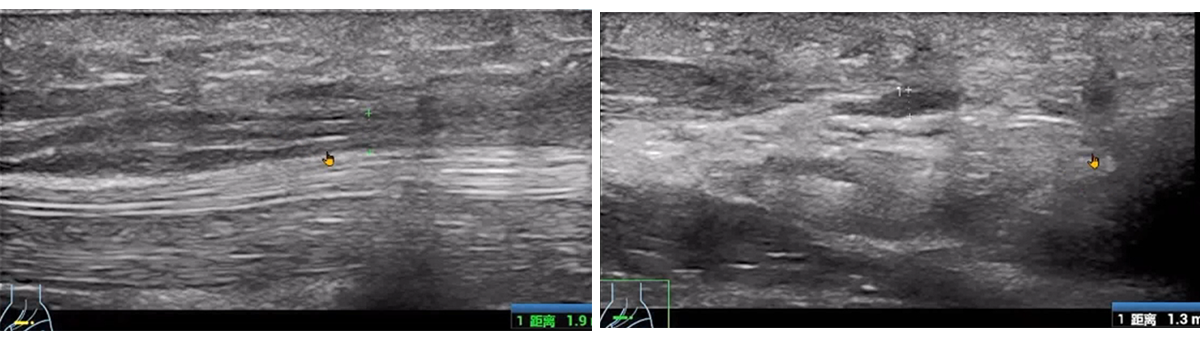

Post-surgery, the patient reported thumb pain, movement restriction, and numbness in the hand.

The ultrasound revealed carpal tunnel syndrome with synovial cysts compressing the recurrent motor branch of the median nerve.

For medical professionals looking to buy a handheld ultrasound machine, this case highlights the machine' s ability to detect subtle post-surgical complications that could otherwise be missed.